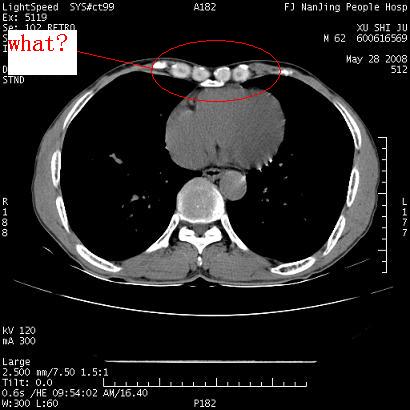

以下是引用杀毒软件在2008-5-28 19:16:00的发言:[br]病灶旁“晕轮征”,考虑肺真菌病

以下是引用qiushi在2008-5-28 20:01:00的发言:[br]空洞周围环状磨玻璃影(日晕征),考虑肺曲霉菌病.

以下是引用clj20在2008-5-28 20:50:00的发言:[br]鉴别诊断:癌性空洞壁结节。建议变换体位ct透视.[br][br]

以下是引用yuhongjun在2008-5-29 4:28:00的发言:[br]空洞周围环状磨玻璃影(日晕征),考虑肺曲霉菌病。支持! [br] [br]

以下是引用lrj在2008-5-28 21:10:00的发言:[br]所示应该是正常结构,是对称的,多个层面都有!也不像是内乳动脉或是肿大淋巴结![br]右下肺渗出性病变伴空洞形成,其洞内见一结节,以下诊断都有可能:1 右下肺曲菌感染, 2右下肺结核空洞形成伴曲菌感染!3右下肺结核空洞伴壁内占位形成,虽说后者发生的几率很低 但作为我们应该多考虑一下吧!最重要的结合临床